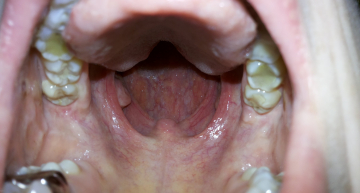

Хронический атрофический фаренгит

Хронический субтрофический ларенготрахеит

Моей маме 62 года. Удалена щитовидная железа в сентябре 2014 года. Лежала в пульмонологии больницы скорой помощи в Минске. Лечили антибиотиками в большом количестве. Начался сильный дисбактериоз, диарея, обострился хронический цистит и вагинит. Также у нее хронический кандидоз - вылечить не получается. При выписке 26 июня 2015 года подхватила новую инфекцию и новое обострение - обострился ларинго-трахеит, бронхит и носоглотка. 2 месяца назад появилась патология носоглотки (скапливается слизь на соединении носа и задней стенки гортани - она постоянно пытается это отхаркивать)